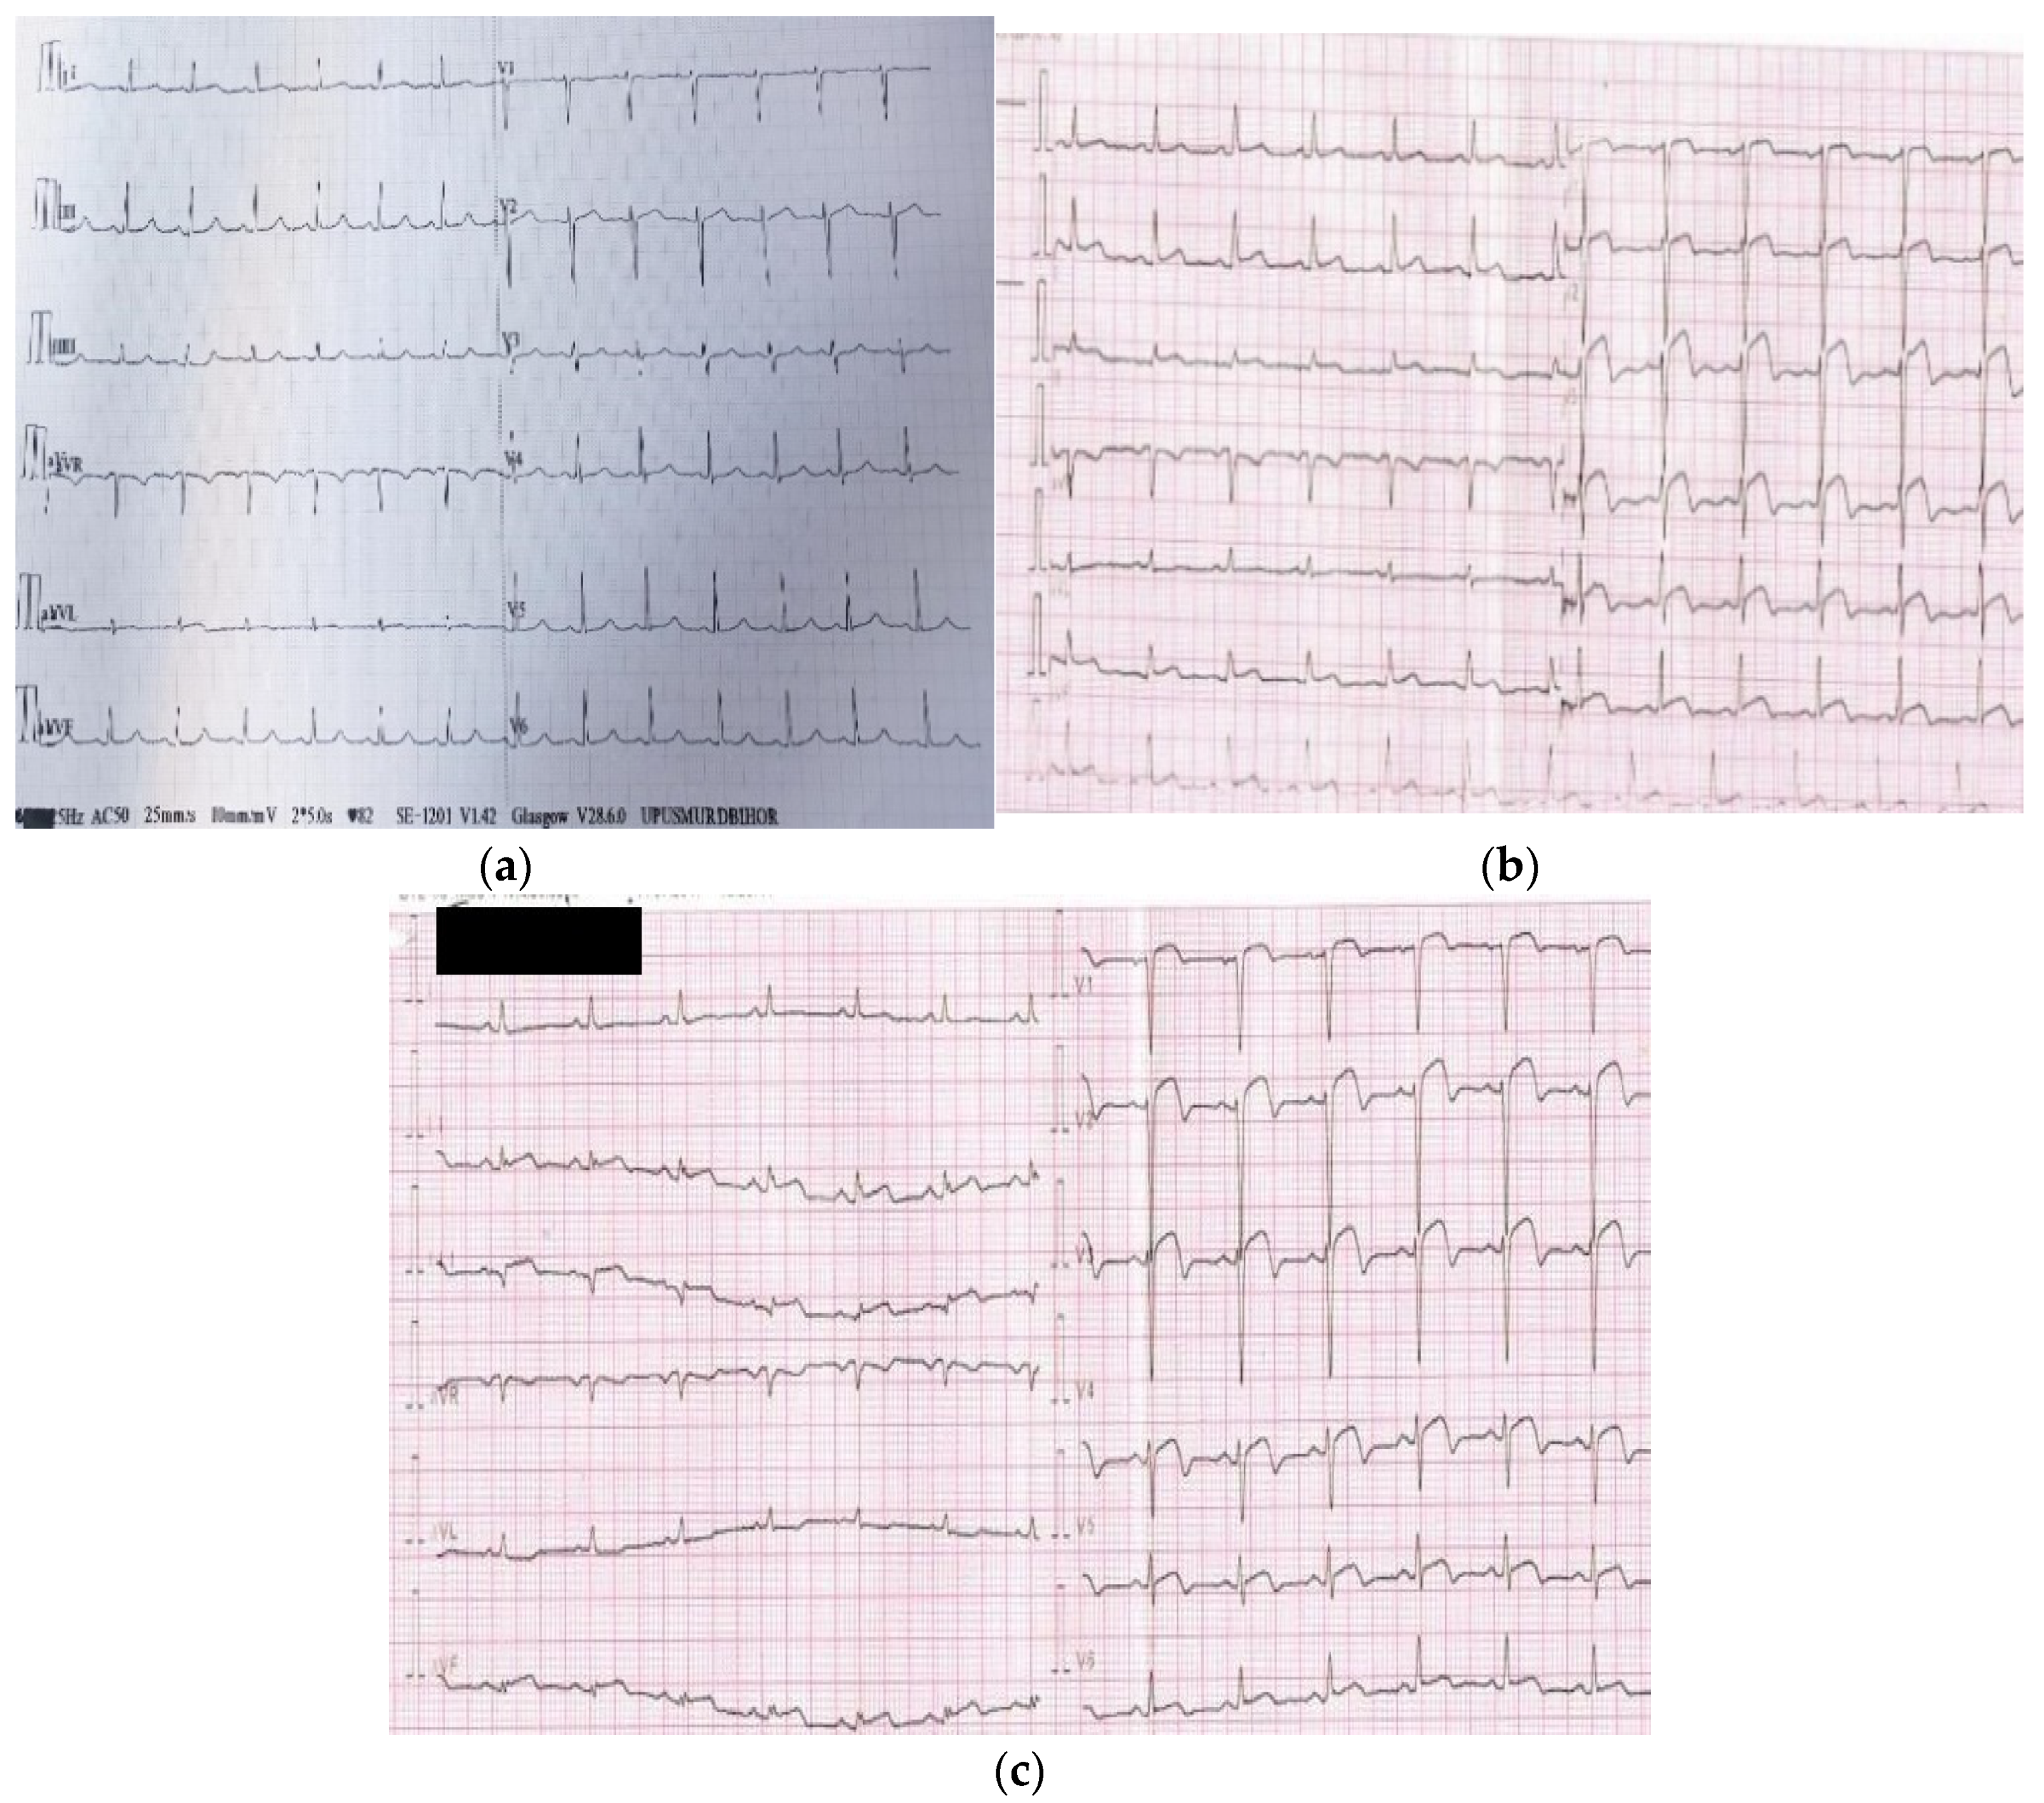

5.1.1. ECG

- Claeys, M.J.; Bosmans, J.; Veenstra, L.; Jorens, P.; De Raedt, H.; Vrints, C.J. Determinants and prognostic implications of persistent ST-segment elevation after primary angioplasty for acute myocardial infarction importance of microvascular reperfusion injury on clinical outcome. Circulation 1999, 99, 1972–1977. [Google Scholar] [CrossRef] [PubMed] [Green Version]

- Tatu-Chițoiu, G. Electrocardiograma in Reperfuzia Miocardica; Editura Medicală Antaeus: Bucharest, Romania, 2014; ISBN 606-8470-08-5. [Google Scholar]